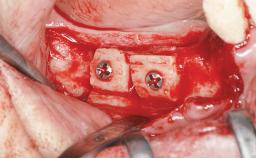

Autologous Block Graft and Guided Bone Regeneration (GBR) for Horizontal Ridge Augmentation in the Posterior Mandible

An 18-year-old man was referred for implant therapy in the posterior mandible to the Department of Oral Surgery and Stomatology (University of Bern, Switzerland). He was healthy and did not smoke. Tooth 35 was congenitally missing, involving a single-tooth edentulous space that offered an adequate mesiodistal dimension for implant placement but exhibited a typical pattern of buccal flattening. A panoramic radiograph was obtained, which revealed a sufficient vertical bone height above the mandibular canal and a normal bone structure in the edentulous area.